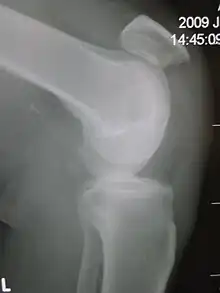

Patellar tendon rupture showing a marked distance between the tibial tuberosity and the bottom of the knee cap.

Patellar tendon rupture can usually be diagnosed by physical examination. The most common signs are: tenderness, the tendon's loss of tone, loss of ability to raise the straight leg and observation of the high-riding patella. Radiographically, patella alta can be detected using the Insall and Salvati method when the patella is shorter than its tendon. Partial tears may be visualized using MRI scans.[4]